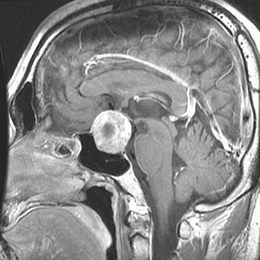

詳しい説明はこちら頭蓋咽頭腫

ラトケ嚢胞と同じく袋を有するできものです。ラトケ嚢胞とは類縁の病気ですが、ラトケ嚢胞よりは腫瘍の性格をもっており、必ず短期間で大きくなります。

通常、目が見えなくなったりホルモン分泌低下により多尿が生じたり全身倦怠感や寒がりになるなどの症状が生じます。

詳しい説明はこちら

頭蓋咽頭腫

まず手術で可能な限り腫瘍を摘出します。経鼻的手術か開頭手術かは腫瘍の場所と大きさによります。採用する手術方法は経鼻的手術が50%、開頭手術が50%くらいです。完全に摘出すれば追加治療は不要ですが、この腫瘍は下垂体に強く癒着していることが多く、完全に摘出すると下垂体機能が低下することも多いため下垂体機能を残すために一部腫瘍を残して、手術後にガンマナイフなどの放射線療法を追加することもあります。